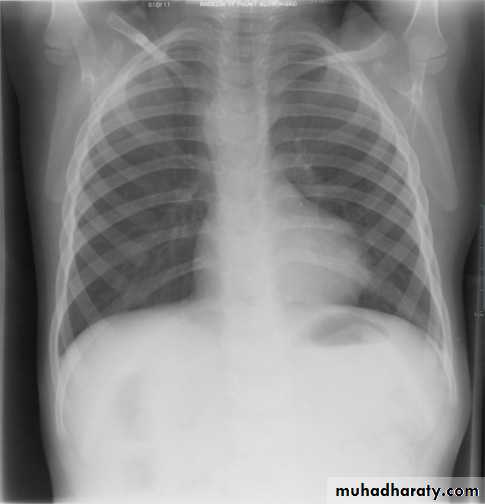

Egg-on-a-string sign ( TGA )

A frontal chest radiograph classically shows cardiomegaly with a cardiac contours classically described as appearing like an egg on a string . There is often an apparent narrowing of the superior mediastinum as result of the aortic and pulmonary arterial configuration .